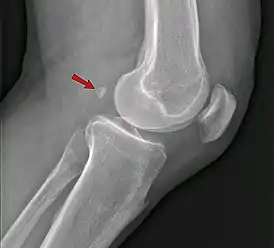

Фабелла — небольшая сесамовидная кость, обнаруженная у некоторых млекопитающих, встроенная в сухожилие боковой головки икроножной мышцы позади латерального мыщелка бедренной кости. Это дополнительная кость, анатомическая вариация, присутствующая у 39 % людей[1][2]. В редких случаях таких костей бывает две или три (fabella bi- или tripartita). Эту кость можно принять за дряблое тело или остеофит. Слово fabella — это латинское уменьшительное от слова faba, означающего «фасоль»[3].

«Фабелла может вызывать заднебоковую боль в колене либо из-за размягчения хряща (chondromalacia fabellae), либо из-за других остеоартрозных изменений на его суставной поверхности»[6].